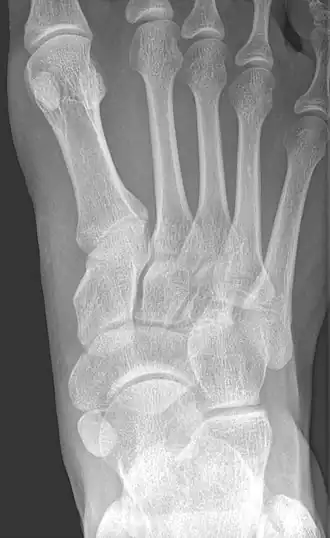

![]() X-ray of the foot showing an accessory navicular bone | |

An accessory navicular bone is an accessory bone of the foot that occasionally develops abnormally in front of the ankle towards the inside of the foot. This bone may be present in approximately 2-14% of the general population and is usually asymptomatic.[1][2][3] When it is symptomatic, surgery may be necessary.